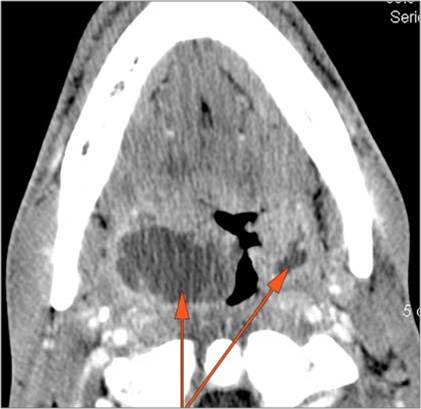

There is an abscess relatively centrally within the lymphoid tissue of the palatine tonsil. [Yes/No]

There is evidence of a developing abscess at the periphery of the lymphoid tissue of the palatine tonsil within the potential peritonsillar space. [Yes/No]

There is edema or abscess within the fat of the adjacent parapharyngeal and retropharyngeal space. [Yes/No]